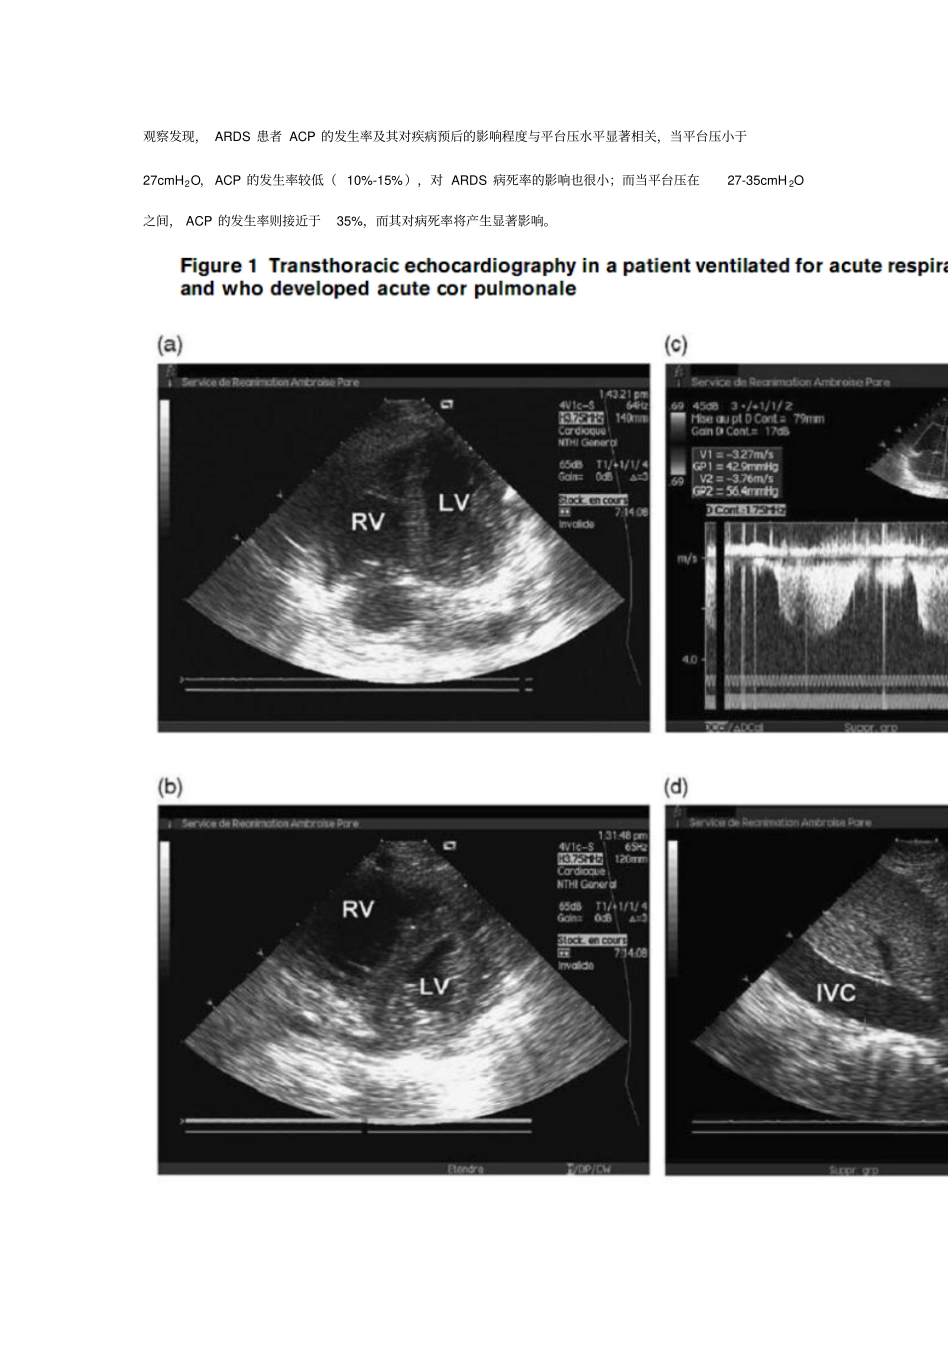

急性呼吸窘迫综合征、机械通气与右心室功能沈锋贵阳医学院Acute respiratory distress syndrome, mechanical ventilation, and right ventricular functionCurrent Opinion in Critical Care (Vol 17,pp30-35.2011 )Koceila Bouferrache and Antoine Vieillard-Baron一、前 言ARDS、机械通气及右心室功能之间有着密切联系。由于ARDS 患者不仅存在肺泡病变,同时也存在肺循环异常,故病程中可伴有右心室功能障碍。众所周知正压通气能影响肺循环,进而导致右心室功能的异常,尤其在如ARDS 的特定情况下更易发生。此外,呼吸机参数设置不当也将影响右心室功能,严重者发生急性肺心病(ACP)。 ACP 一旦发生,反过来将加重ARDS 病情并影响其预后。本文将重点阐述平台压、PEEP 及 PaCO2 影响右室心功能的主要机制,并对右心室功能障碍如何加重ARDS 病情等加以讨论,并提出“右心室功能保护性通气策略”。二、 ARDS 病程中右心室功能障碍发生率及其对ARDS 预后的评估价值ARDS 患者病程中常伴有右心室功能障碍,严重者发展为急性肺心病(ACP )。ACP 的病理变化主要包括右心室扩张及收缩期室间隔存在矛盾运动(Figure 1)。前者反映了右心室舒张期容量超负荷,而后者则反映右心室收缩期超负荷。Vieillard-Baron 对 75 例接受保护性机械通气ARDS 患者观察发现, ACP 发生率为 25%。Mekontso-Dessap 等报道, 203 例 ARDS 患者同样也接受保护性通气策略(平均 PEEP10cmH2O,平台压 23cmH 2O),其 ACP 发生率 22%,且 ACP 患者其卵圆孔开放性分流发生率将显著增加( 34% versus 15%), ARDS 治疗效果也较差,包括呼吸机带机时间延长等。Osman 等回顾性分析发现,145 例 ARDS患者经肺动脉导管监测有27%患者发生右心室功能障碍,且右心室功能障碍与病死率具有相关性。Monchi等应用右心导管技术,对大量未接受保护性通气ARDS 患者观察后发现右心室功能障碍为导致死亡的独立危险因素。Vieillard-Baron等通过观察机械通气中ARDS 患者 ACP 的发生规律可寻找防止ACP 发生的呼吸机参数设置要点,必要时采用俯卧位通气。Jardin 和 Vieillard-Baron 通过超声心动图对352 例 ARDS 患者观察发现, ARDS 患者 ACP 的发生率及其对疾病预后的影响程度与平台压水平显著相关,当平台压小于27cmH2O, ACP 的发生率较低( 10%-15%),对 ARDS 病死率的影响也很小;而当平台压在27-35cmH...